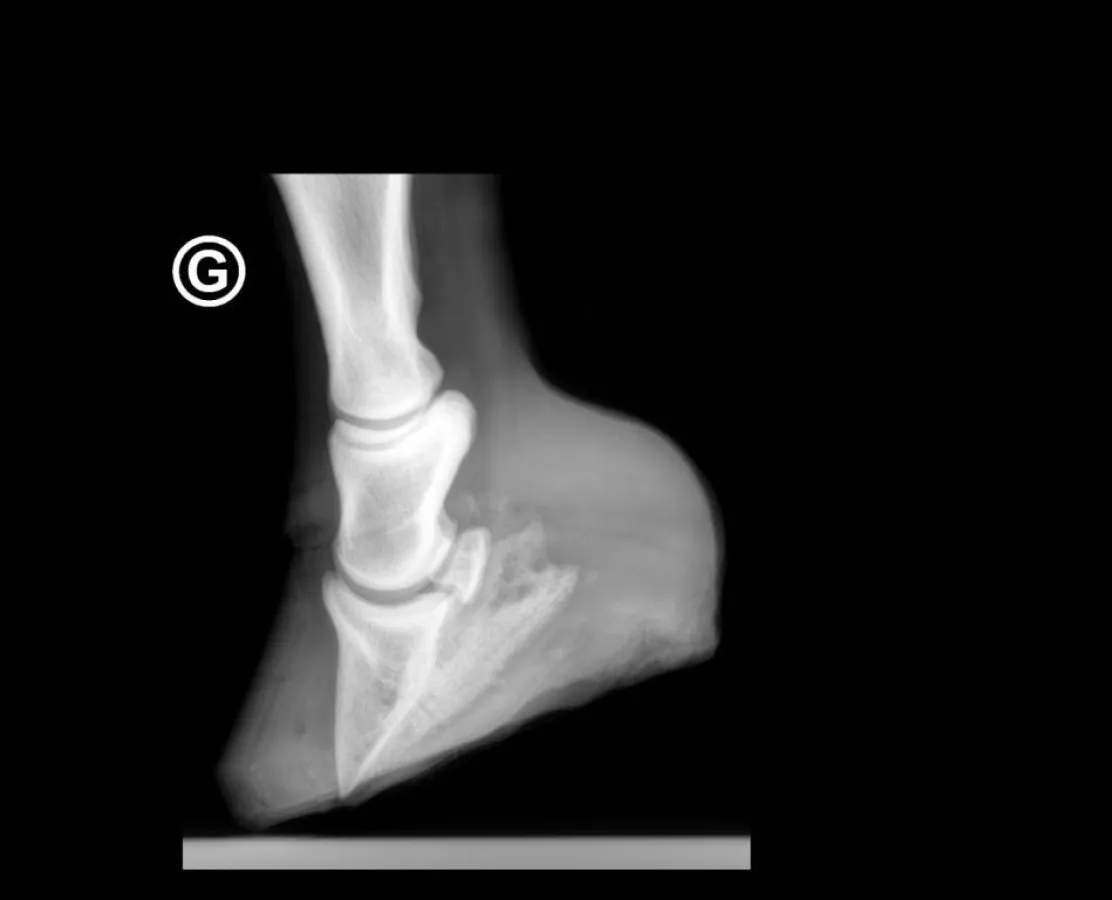

Wir möchten Ihnen noch aufzeigen, was mit dieser Methode gemacht werden kann. Das obenstehende Röntgenbild zeigt die Situation einer Schweizer Warmblutstute mit einem 14-tägigen Fohlen bei Fuss. Aus Sicht mehrerer Mediziner war die Stute verloren, da sie kurz vor einem Hufbeindurchbruch stand. Zudem begann von der Mitte her der Kronrand aufzuplatzen, was im Normalfalle auf das „Ausschuhen“ eines Hufrehepferdes hindeutet.

Nur in einer aufwendigen „Kühlaktion“ - über 14 Tage - konnte die Stute gerettet werden. Sie ist, zusammen mit ihrem Fohlen wohlauf und bewegt sich mit Hufschuhen einwandfrei. Wir sind uns bewusst, dass das Anbringen von Eiswürfeln jede Stunde – besonders Nachts – ein grosses Engagement erfordert. Der Erfolg wird jedoch für alle Beteiligten die schönste Belohnung sein!